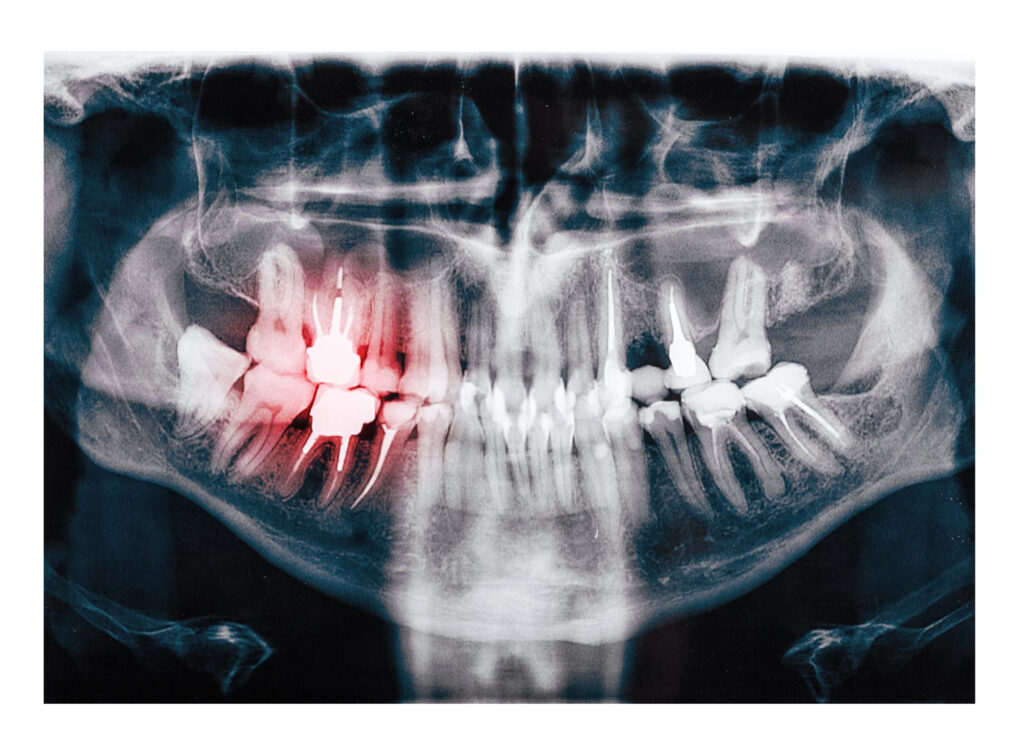

At Healthy Smiles Dental, we prioritize your oral health. Our dentists utilize X-rays to examine your teeth, and supporting structures. These images help our clinicians in detecting cavities, missing teeth, abnormal growth, bone damage, cysts, tumors, etc.

These images play a crucial role in identifying various issues, including cavities, impacted teeth, missing teeth, abnormal growth, bone damage, cysts, tumors, etc. The information provided by X-rays is crucial for planning treatments for dental issues.